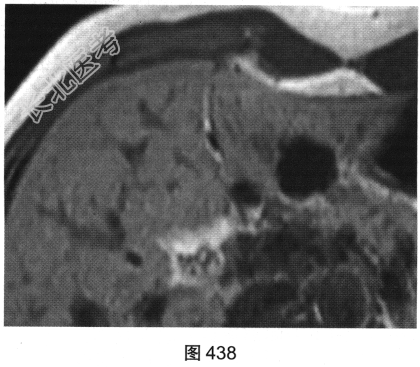

- [材料题] 患者女性,44岁,HBV感染史6年。查体:腹平软,右上腹无压痛,无反跳痛,肝脾肋下未及,Murphy征阴性,肝浊音界存在,肝上界位于右锁骨中线第五肋间,肝区无叩击痛,移动性浊音阴性。实验室检查:肝功能未见异常,AFP(一)。患者MRI平扫如图438、图439所示。

- 多项选择题1.MRI平扫图中可见哪些影像学发现( )

A、T1WI上呈均匀低信号

B、T1WI上呈均匀等信号

C、平扫肝左叶可见一类圆形病变

D、病变与周围分界欠清晰

E、T2WI上呈均匀高信号

F、T2WI上呈均匀低信号